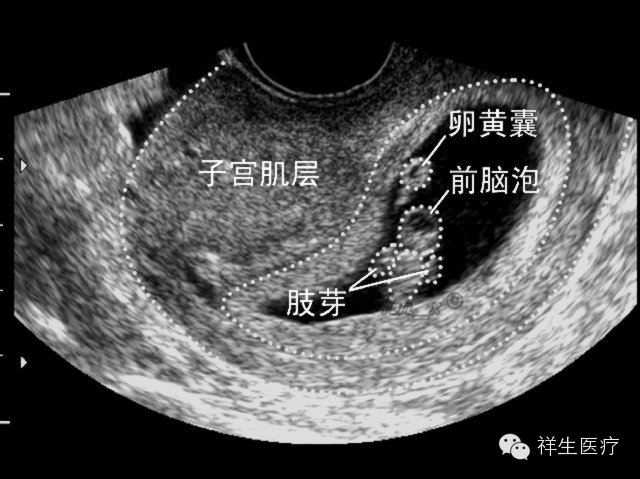

5.孕9周:此时开始称为胎儿。各部分发展趋于完善,经阴道超声扫查已能观察大部分结构。

6.孕10周:这时候可以看见宝宝颈背部的皮肤级皮下组织啦,还可以数出宝宝的手指,肢体活动相当活跃。